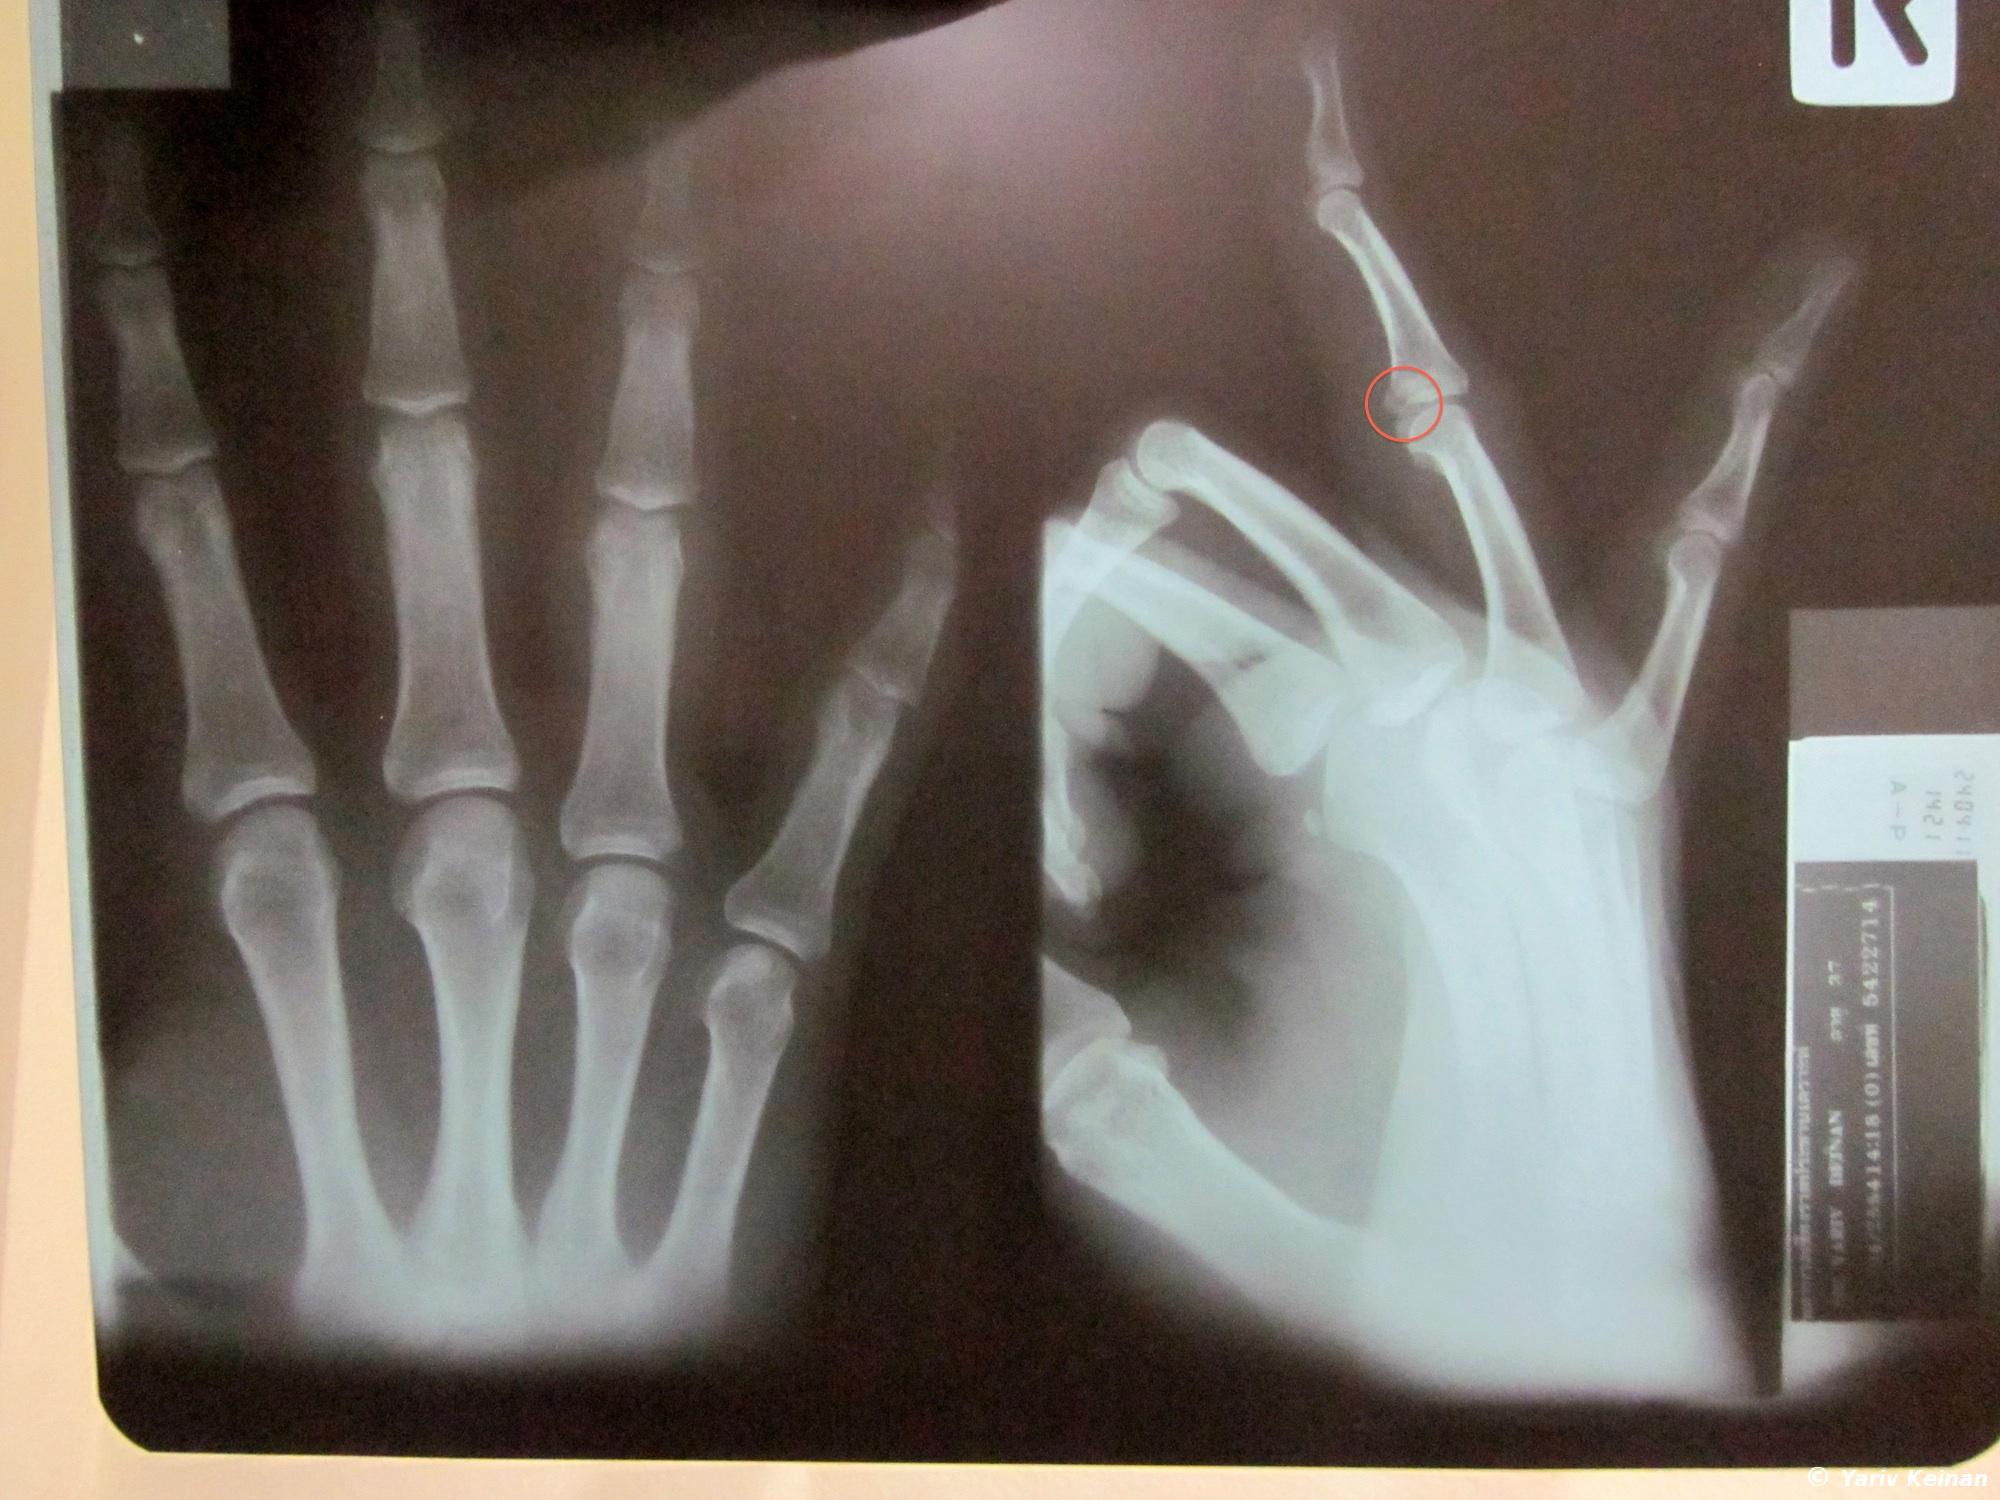

So now I am back in Thailand after a smooth border crossing this morning and a short ride to Chiang Rai. I like this town, it has a really nice vibe in the backpackers area. Once here I went on a different type of experience – the hospital experience. I tripped over some steps back in Vientiane over 2 weeks ago and hurt my ring figure. It wasn’t so bad but then I tripped again during the jungle track in Luang Nam Tha and it got a bit worse. Since there are no decent hospitals in the entire country of Laos anyway (not to mention the north) I decided to just make a ghetto splint from a popsicle stick and have it examined in Thailand. Mind you that it didn’t hurt much and I was able to easily ride a motorcycle for 2 days AND zip-line through the jungle safely, but it was better to have it looked at by a doctor. I thought I just tore or hurt a ligament but it turned out that I actually fractured the middle bone of my right ring finger.

So now I have this huge thing on my hand for 4 weeks even though there is hardly any pain (unless I flex my finger all the way) and I feel very ridiculous. Oh well. BTW, the bill for the medical treatment was:

– X-Ray